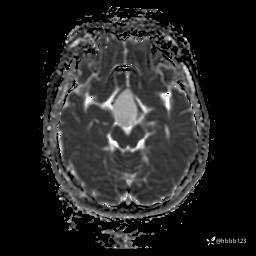

DWI:

ADC: